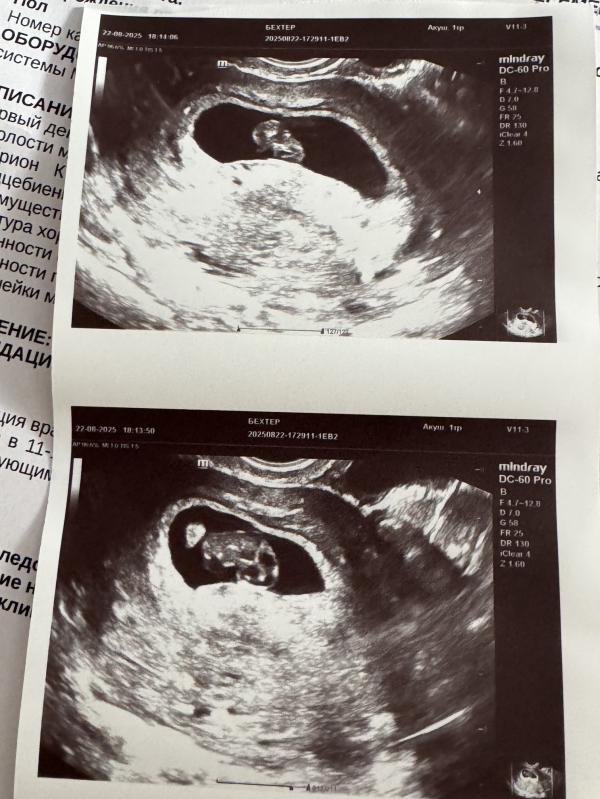

Как трепетно увидеть стук сердечка на экране монитора УЗИ🥹♥️🤞🏻

Оказывается, мы догнали срок и никакой поздней овуляции у нас не было, просто на тот момент так разглядели 🙈

Так что мы соответствуем всем нормам и растем💪🏻

Супруг так хотел со мной зайти на узи и послушать сердечко, но врач сказала использование допплера на этом сроке опасно для малыша⛔️

Потерпим до 1го скрининга 🥰